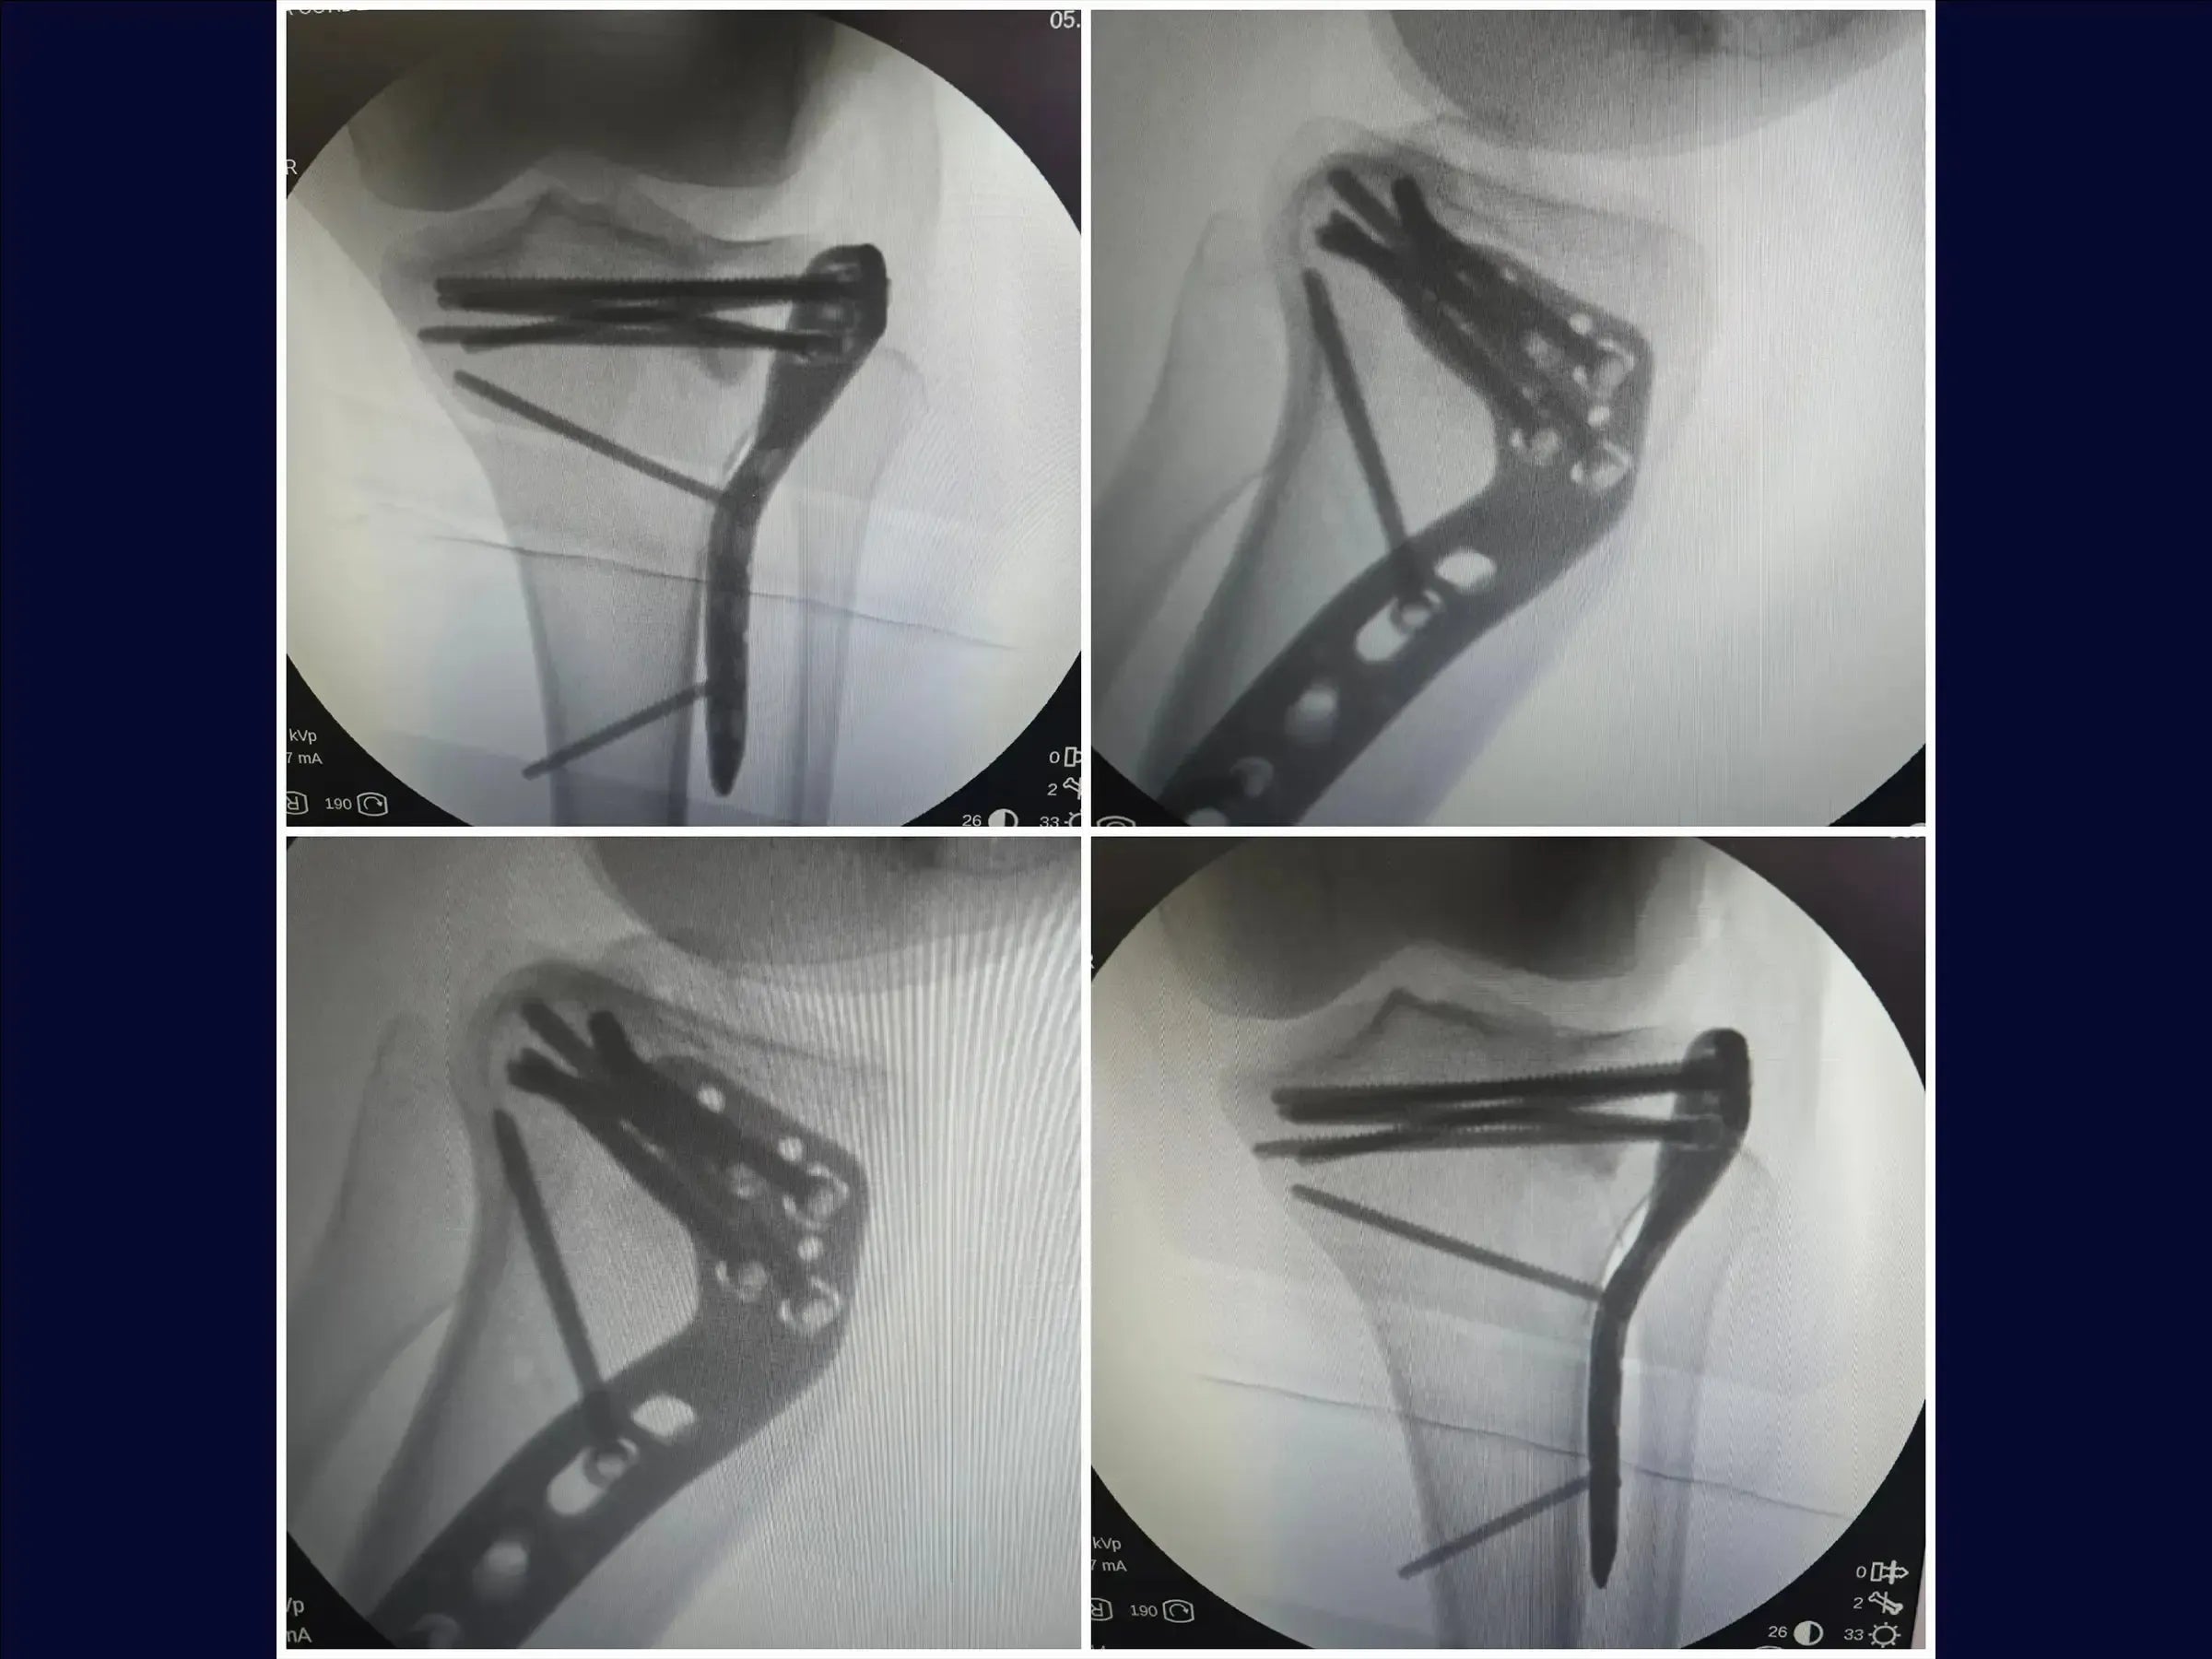

- Técnica de osteotomía incompleta (elástica) para levantar el fragmento hundido.

- Fijación con placa y tornillos para reducción y estabilización anatómica.

- Osteotomía Incompleta (Elástica): Aprendizaje de una técnica que preserva la corteza anterolateral inferior, permitiendo la elevación elástica del fragmento sin crear un segmento suelto, lo que simplifica la reducción y estabilización.

- Estrategia de Fijación Estable: Aplicación de la placa con tornillo en un punto estratégico para la compresión inicial, seguido de la inserción de tornillos bloqueados subcondrales , formando una red de soporte articular.